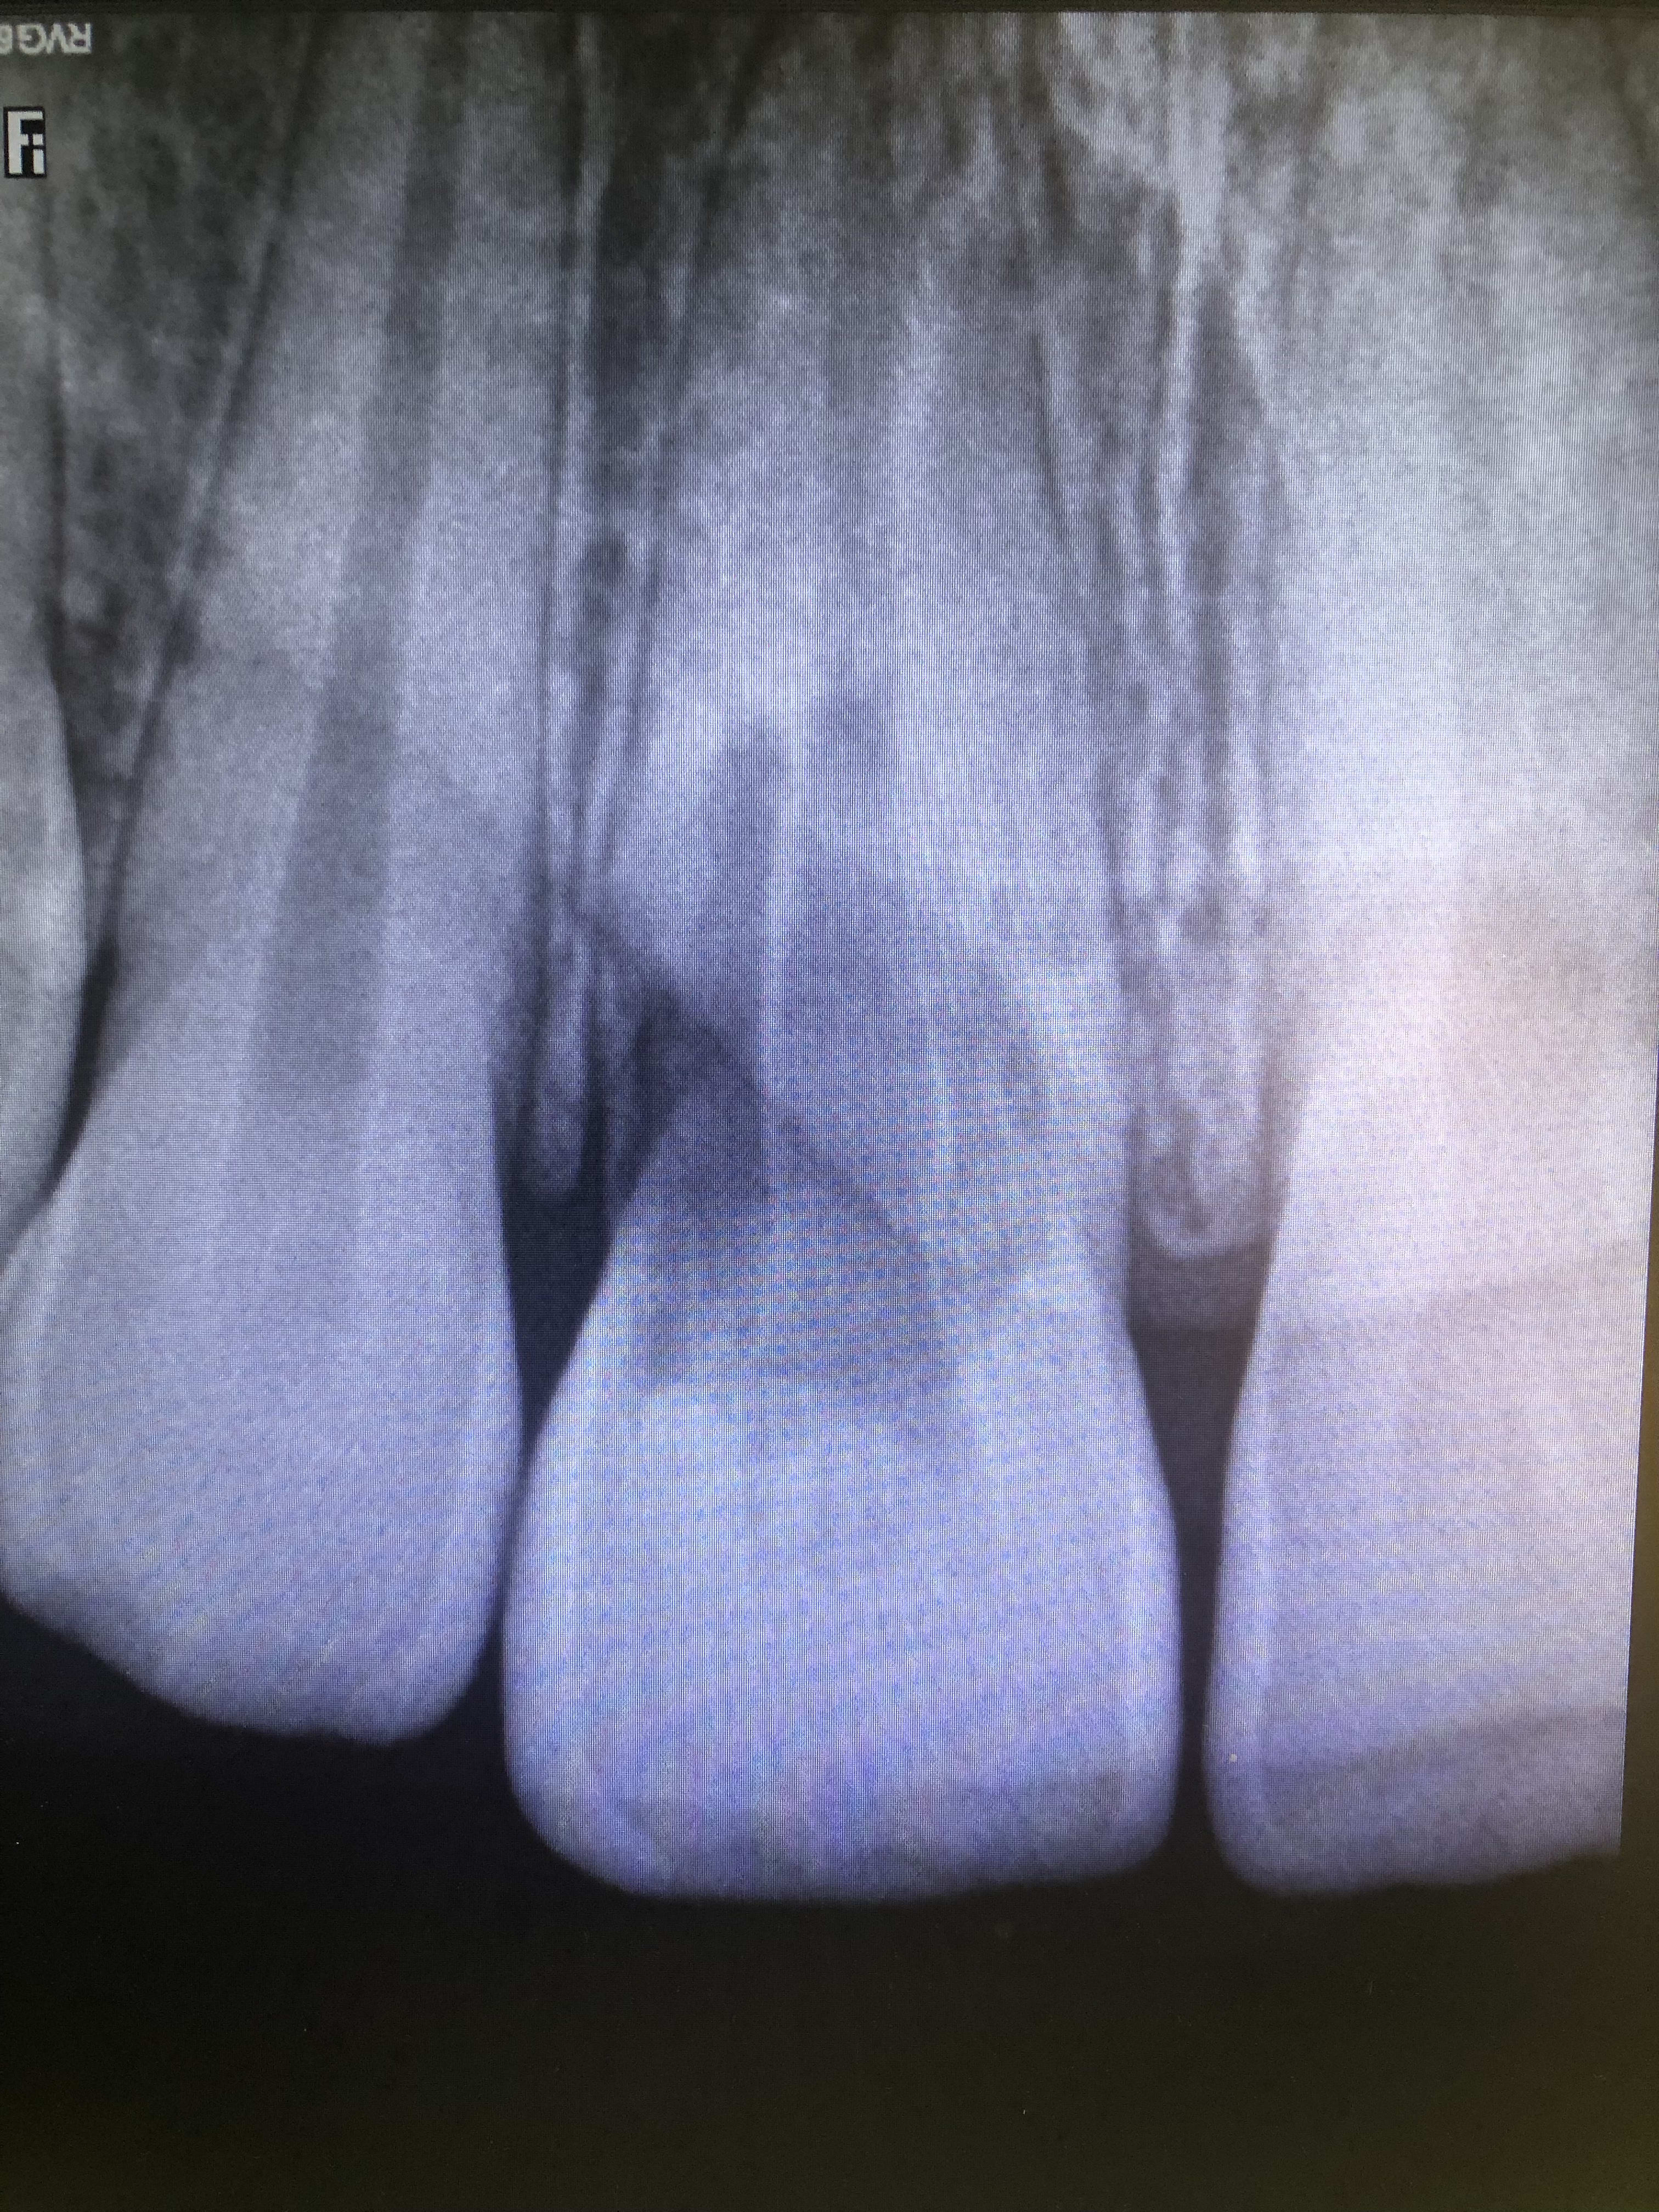

Bon comme tout le monde s’en branle de ce qui est arrivé au gamin au bout de 5 ans. Je m’le finis.

Radio pré op.......je le mets où l’IC????

Dc79d14c 234c 44b6 8d09 83c2a6f2a445 whckna - Eugenol